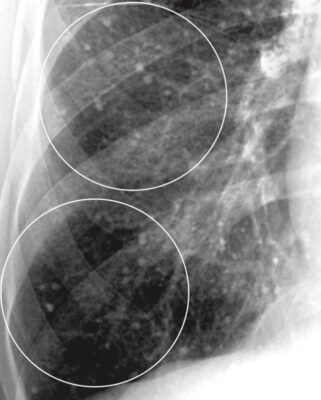

Phù phế nang phổi (Pulmonary alveolar edema)

- Phù phế nang phổi cấp tính điển hình thường tạo ra bệnh lý khoang chứa khí hai bên, quanh rốn phổi, đôi khi được mô tả là có hình dạng cánh dơi (bat-wing) hoặc cánh thiên thần (angel-wing) (Hình 6).

- Biểu hiện có thể không đối xứng nhưng thường không chỉ một bên. Phù phổi có nguồn gốc từ tim thường phối hợp với tràn dịch màng phổi và chất dịch làm dày các rãnh lớn và rãnh bé.

- Bởi vì chất dịch không chỉ lấp đầy các khoang chứa khí mà còn cả các phế quản, nên thường không có hình ảnh phế quản chứa khí trong phù phế nang phổi. Thường thì phù phổi hết nhanh sau khi điều trị (<48 giờ).